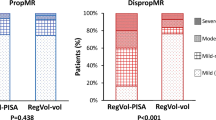

The well-known EROA–LVEDV diagram adapted according to Grayburn et al. [12] should illustrate the proportionality between EROA and LVEDV in patients with severe FMR with a border area. Below this area non severe FMR is characterized. Above this area Grayburn et al. proposed to use the term “disproportionate” severe FMR [12]. Grayburn et al. described the diagnostic scenario that “physicians should seek to determine whether the estimated degree of MR is expected or proportionate to the degree of LV dilatation, or alternatively, whether the severity of MR is unexpected or disproportionate to the degree of LV enlargement” [12].

If the mean values of EROA and LVEDV of the recent TMVR trials [1,2,3] are put into the diagram, the brightened colored dots represent the respective relationships (Fig. 5). However, if these values are corrected with respect to plausible hemodynamics—that means RegVolMV or EROA were reduced to ensure at least borderline CI of 2.2 l/min/m2—all these brightened dots shift into the area of non-severe FMR (colored dots in Fig. 5).

The relation between effective regurgitant orifice area (EROA) and left ventricular (LV) end-diastolic volume (LVEDV) at a LV ejection fraction (LVEF) about 30% [6]: the arrows illustrate the respective calculated EROAs presented in recent transcatheter mitral valve repair (TMVR) trials reduced by the amount in relation to a regurgitant volume (RegVolMV), which ensure at least a cardiac index (CI) > 2.2 l/min/m2. Mean values of EROA and LVEDV are given for green hollow dots COAPT [2, 10, 12], blue hollow dots MITRA-FR [1], and pink hollow dots REDUCE-FMR (assumed mean EROA of 0.26 cm2) [3]. If the EROA is reduced according to laws of rheology and physics, the EROAs of the filled circles have to be assumed in the recent TMVR trials (green dots COAPT, blue dots MITRA-FR, and orange dots REDUCE-FMR) (additional explanations in the text)

In all figures two dots are presented for the COAPT trial. The two dots are explained by the values reported in the literature about COAPT [2, 4]. The first reported LVSVtot by planimetry in COAPT was 51 ml and the RegVolMV was 59 ml which suggests overestimation of EROA and RegVolMV, underestimation of LVEDV, or both due to the impossibility of the specified values [2]. If 51 ml as LVSVeff in the presence of 60 ml of LVSVtot are assumed, a fully different scenario with a mild FMR of 8 ml with a corresponding RF of 14% is described (device cohort).